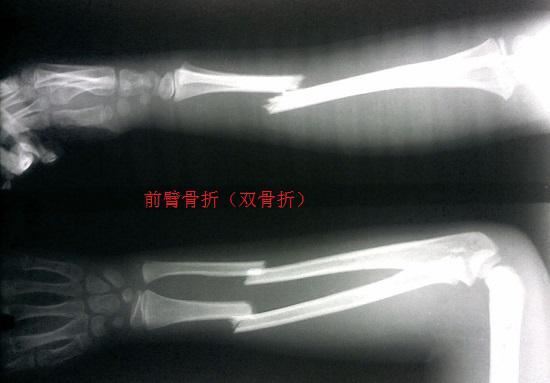

前臂骨折(双骨折)

前臂即胳膊的后半段,即从肘关节到腕关节的部分,主要由尺骨和桡骨承重。前臂骨折即尺骨骨折和桡骨骨折。根据骨折位置的不同,可分为孟氏骨折(尺骨干和桡骨干上三分之一部分的骨折,包括桡骨头的脱位;可进一步细分,具体见下)、盖氏骨折(桡骨干和尺骨干下三分之一骨折,包括尺骨末端的脱位)和桡骨远端骨折(桡骨靠近腕关节处的骨折)。

和其他所有骨折一样,前臂骨折后是否要实施手术治疗,主要取决于骨折后断端是否能够保持稳定。前臂骨折后,如果断端能够进行高吻合度的手法复位,复位后通过外固定的方式能够保持稳定不移位,就不需要实施切开后的复位和固定。反之,如果骨折后断端因为碎块较多、软组织嵌入、肌肉张力等原因难以吻合并保持,就要考虑实施手术治疗。不同类型的前臂骨折,应结合患者情况实施合理的治疗方案。具体如下所列。